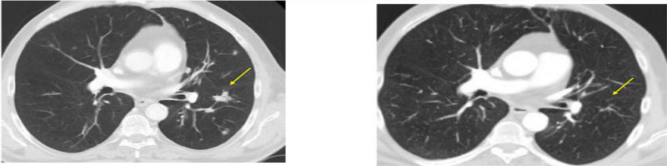

3. 靶向NY-ESO-1的TCR-T疗效也不错。下面是一例接受HPV致癌蛋白TCR-T技术后肿瘤大面积缩小、消失的肛管癌患者治疗前后的影像学片子对比图: